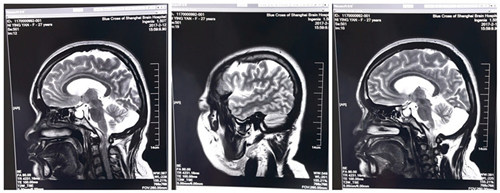

术前:双侧侧脑室旁、半卵圆中心及额顶叶多发灶

“患者的情况,外科手术确实不好做,术前脑电监测双侧都有,放电复杂,范围广,不好分析,一刀下去难以到位,再加上患者有肾病,肝功能不好,体质又不太好,吃药容易过敏,术后的风险、麻醉的风险等等潜在的风险特别大。”医生边分析边解释,“放电部位广,开颅开得大,不仅感染的风险、出血的风险增加,而且手术时间长,病人麻醉的风险也增加,术后出现血管痉挛、出血、感染、肝肾功能衰竭等并发症的概率也更大了。”

“为了手术的顺利进行,我们术前进行了反复监测,多次仔细评估,抓了几次发作,起源都是从左侧开始,然后我们一点点的缩小、锁定病灶范围,并且尽可能的精细化。”术前,脑电监测室的崔丽华主任团队费了很多功夫,凭着过硬的专业素养,最终基本锁定了病灶范围。

医生及团队手术进行中

术前各项准备工作准备周全后,3月2日,倪红的手术顺利进行。手术全麻,以左侧为主。术中见脑部发育不良,脑回肥大,皮层电极反复监测,额叶中央前区、中央区、颞叶散及颞中回深部均见异常放电节律,仔细剥离粘连组织并分区切除病变组织,再次脑电检测显示暴露区无异常放电,术毕,功能区重要血管保护完好,患者安返ICU进行术后监护。

术后复查脑电,“从复查结果看,左侧正常,右侧有少许,临床发作没有,癫痫症状得到明显改善,患者的长期效果应该是可以的。”郭医生说。